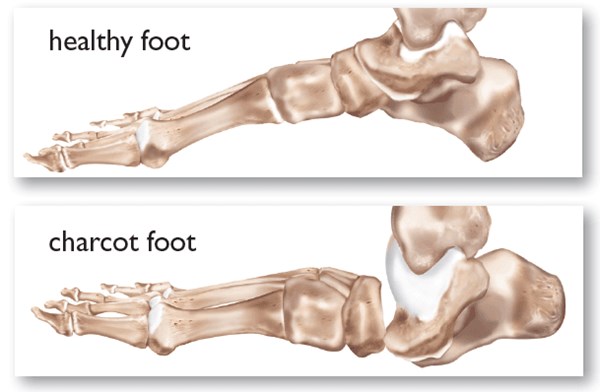

• Foot deformities caused by motor neuropathy (e.g., claw or hammer toes) or neuropathic fractures (e.g, Charcot arthropathy).[68] See section “Assessment - Physical Examination” below.

• Charcot arthropathy: In this syndrome, also known as “Charcot foot”, patients with DPN develop muscle atrophy, which leads to joint instability. Minimal or unperceived trauma results in fractures/dislocations of bones and joints. In the acute stage, there is inflammation and bone reabsorption, which weakens bones. When Charcot arthropathy becomes chronic, residual foot deformities are frequently present. The arch collapses and the foot may develop a ‘rocker bottom’ appearance. Foot deformities can lead to high pressure on areas that are not suited for weight bearing or on areas in contact with improper footwear, which will result in foot ulcers [8][68]. See “Assessment - Physical Examination - Musculoskeletal: Charcot Arthropathy”

• Charcot arthropathy: occurs in the neuropathic foot and most often affects the midfoot (tarsus and tarsometatarsal joints). In its acute phase it may present as a unilateral red, hot, swollen, flat foot with profound deformity. DFUs may or may not be present [64]. In its chronic phase, residual foot deformities are frequently present. Figure 3, Figure 4 and Figure 5.

Figure 3. Charcot arthropathy

Figure 4. Charcot arthropathy clinical examination. Diffuse swelling is noted to the left foot in a typical, Charcot presentation in a 45-year-old male diabetic. The swelling is diffuse and non-painful. [77]

Figure 5. Charcot arthropathy X-ray. Oblique view X-ray in a 45-year-old male diabetic revealed a divergent, Lisfranc dislocation of the first metatarsal with associated lesser metatarsal fractures. [78]